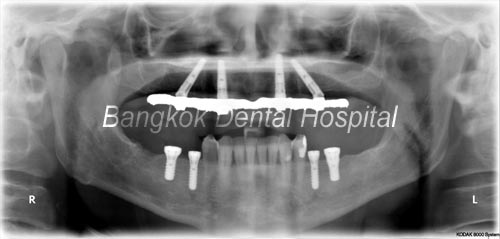

dopo

dopo all-on-4 x-ray